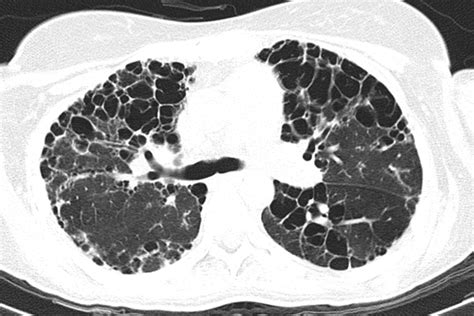

High-Resolution CT (HRCT) To visualize the architectural changes and scarring pattern in the lungs.

At their core, autoimmune lung conditions occur when an overactive immune system triggers chronic inflammation within the lung parenchyma, airways, or the pleura (the lining of the lungs). This inflammation can result in scarring, known as pulmonary fibrosis, or other structural damages that hinder the lungs' ability to exchange oxygen and carbon dioxide effectively. Many of these conditions occur as part of a systemic disease, meaning they affect other parts of the body simultaneously, such as joints, skin, or muscles.

• Sjögren’s Syndrome: Can lead to airway disease or cystic lung changes.